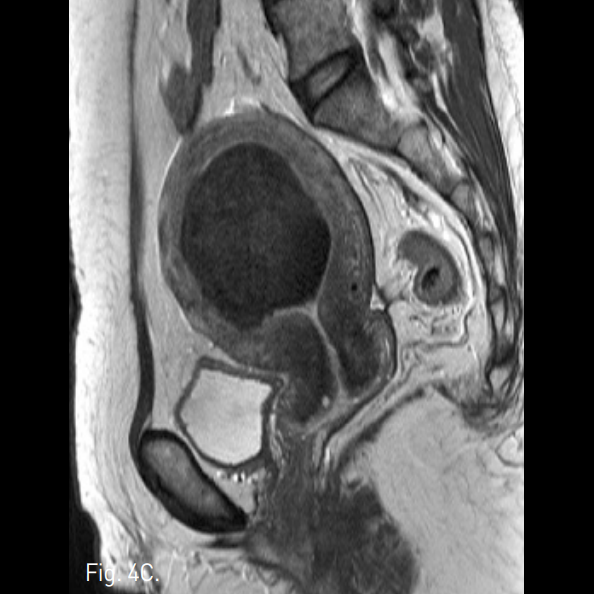

Fig. 4

A-C. Three months follow-up T2-weigh ted transverse (A), coronal (B), sagittal (C) MR images show a huge mass of low signal intensity.

D. Three months follow-up T1-weighted MR image with contrast enhancement shows a non-enhancing uterine mass.